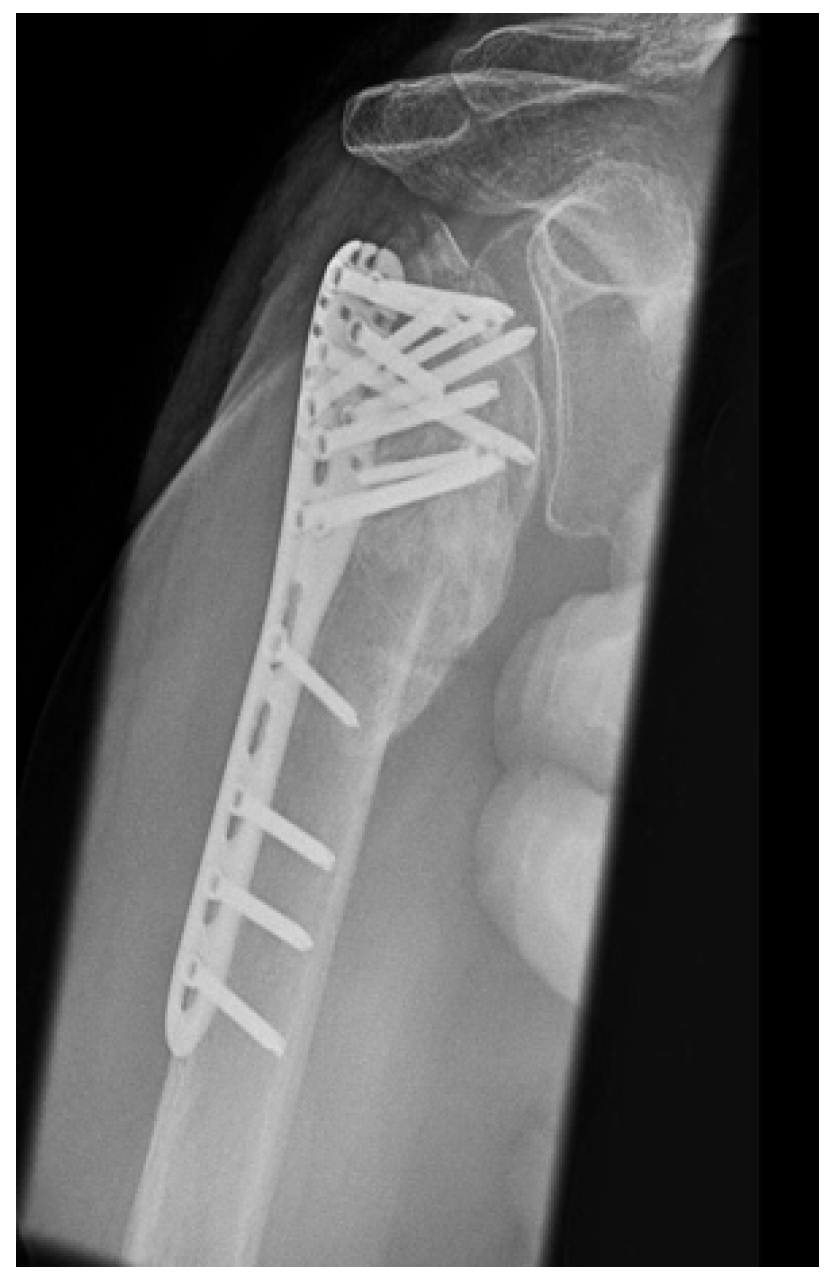

| Complication Type | Exemplary Images by X-rays or Pattern Images | Definition |

|---|---|---|

| 3 | ![]() | Type 3 describes a displacement of the angular stable plate osteosynthesis with screw cutout/fracture avulsion in the humeral shaft region, while the humeral head position remains intact. |